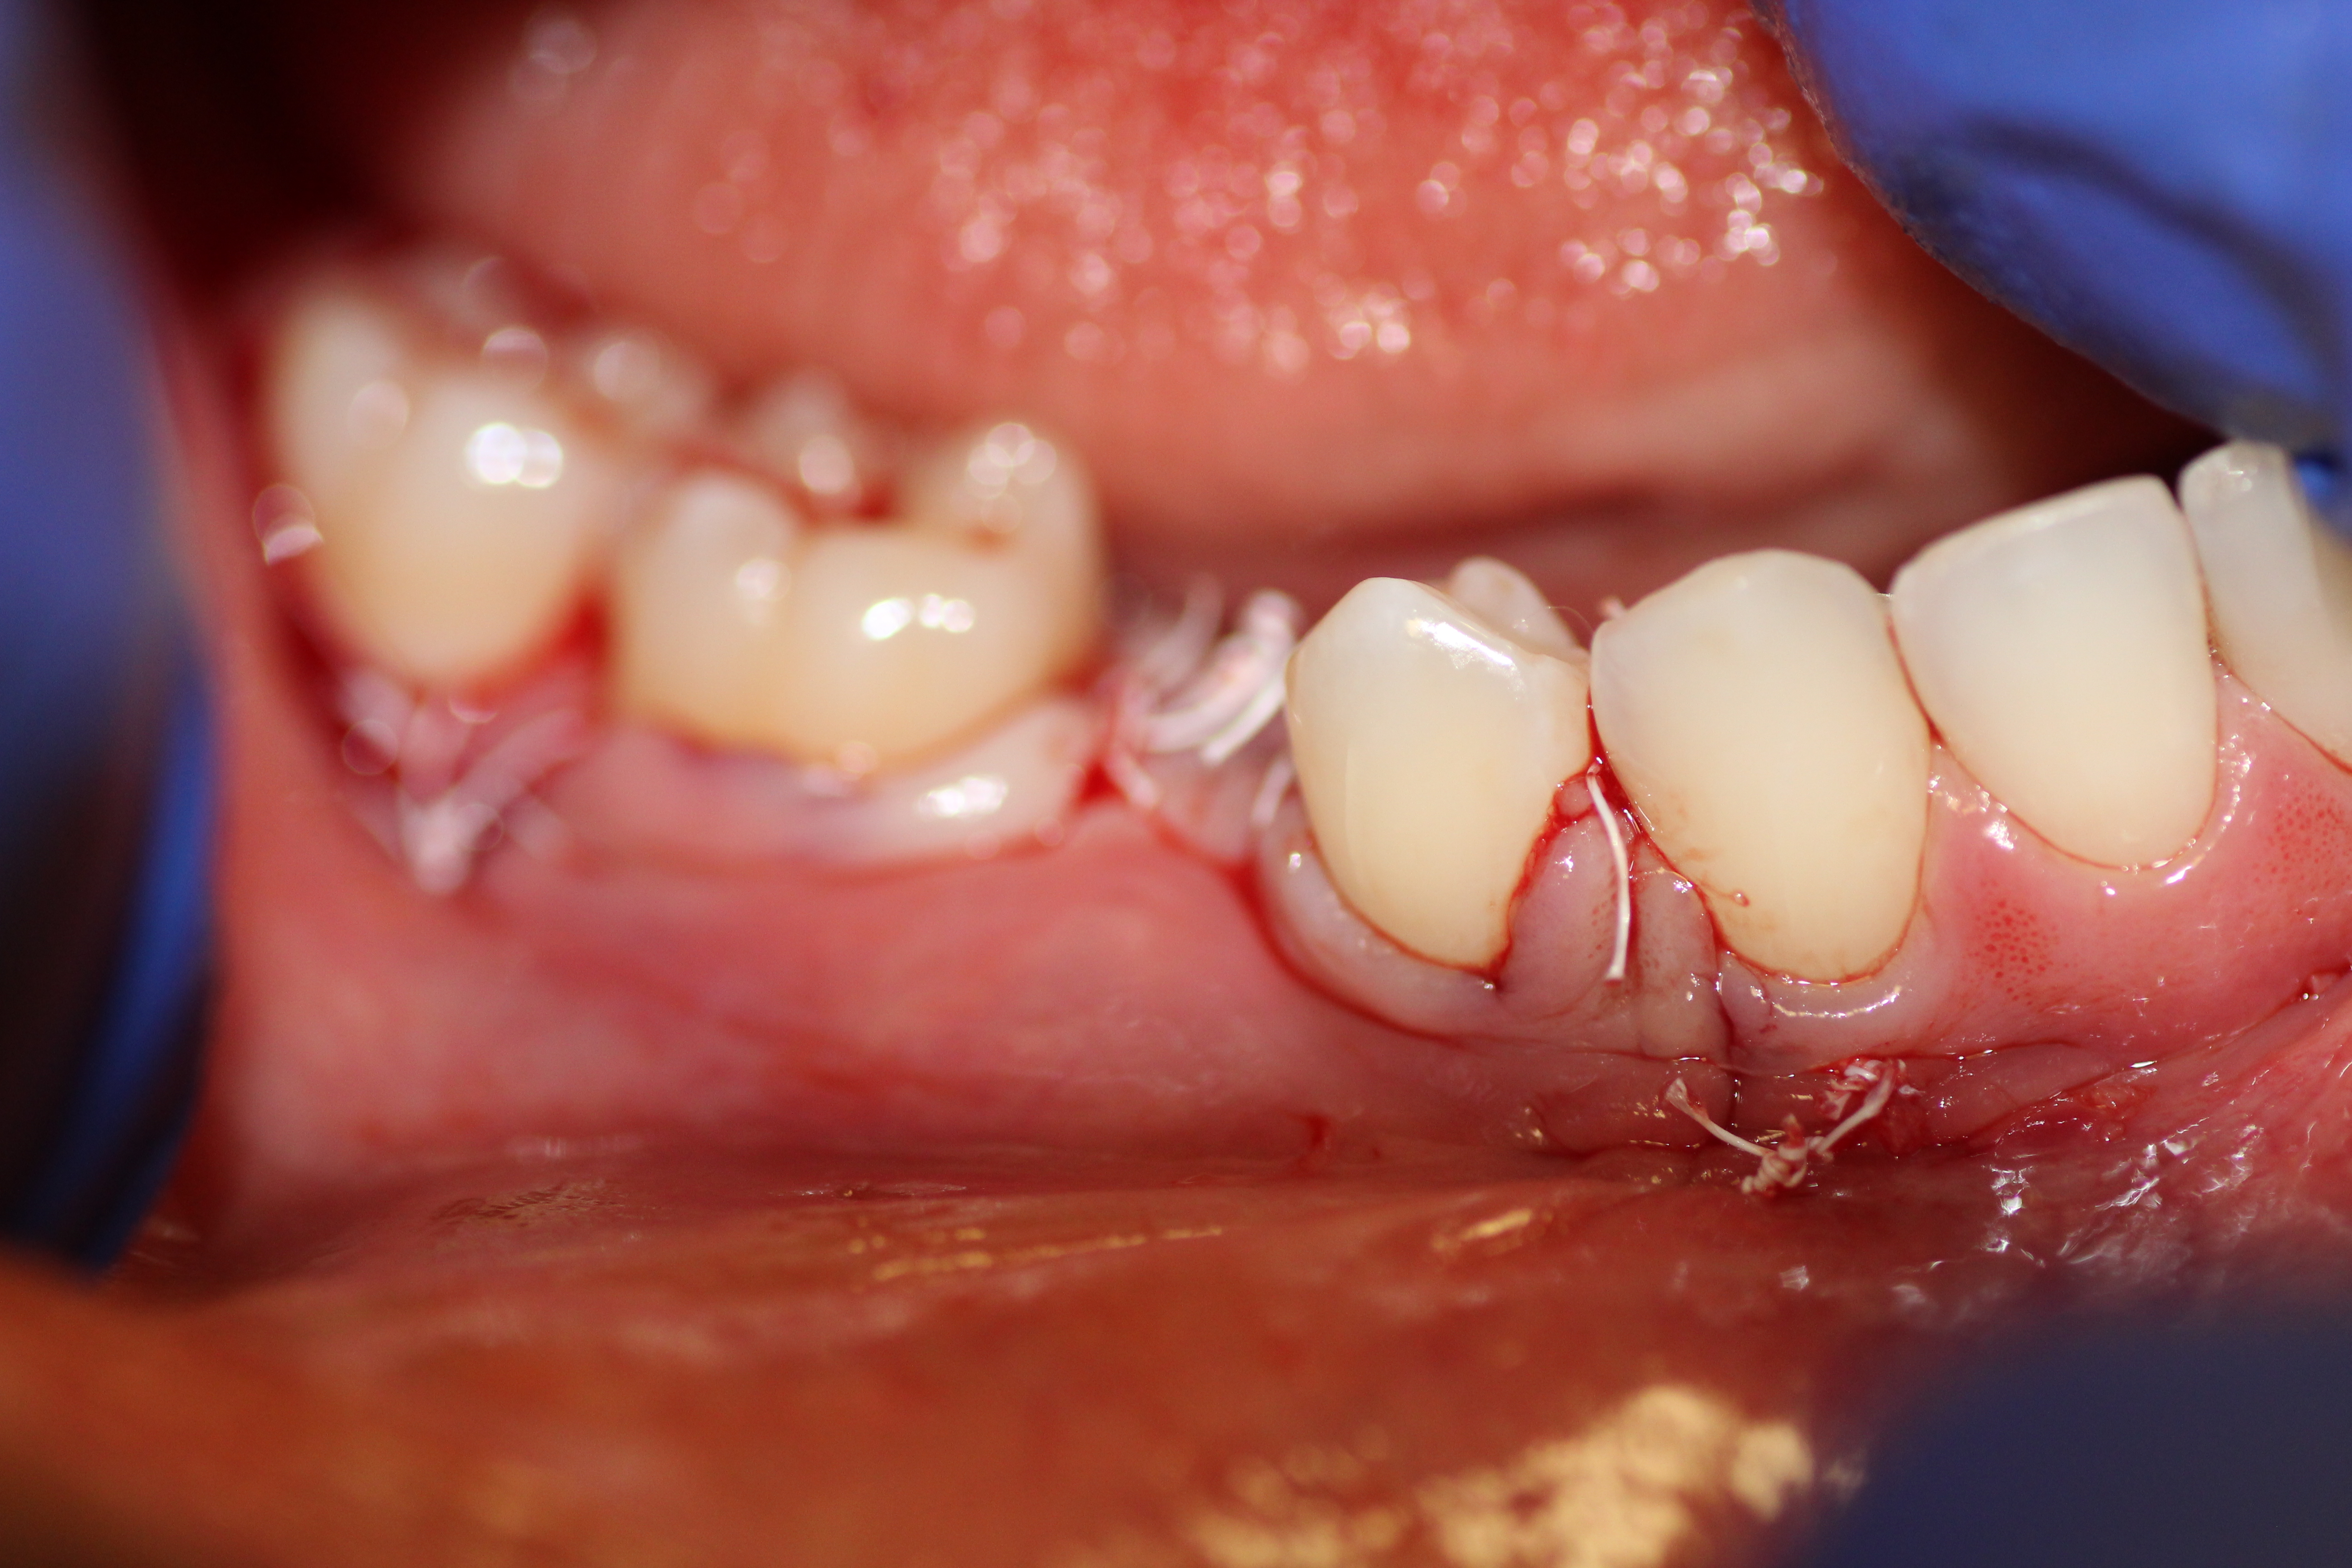

Immediate placement with bone guided regeneration.

- Surtured after surgery.